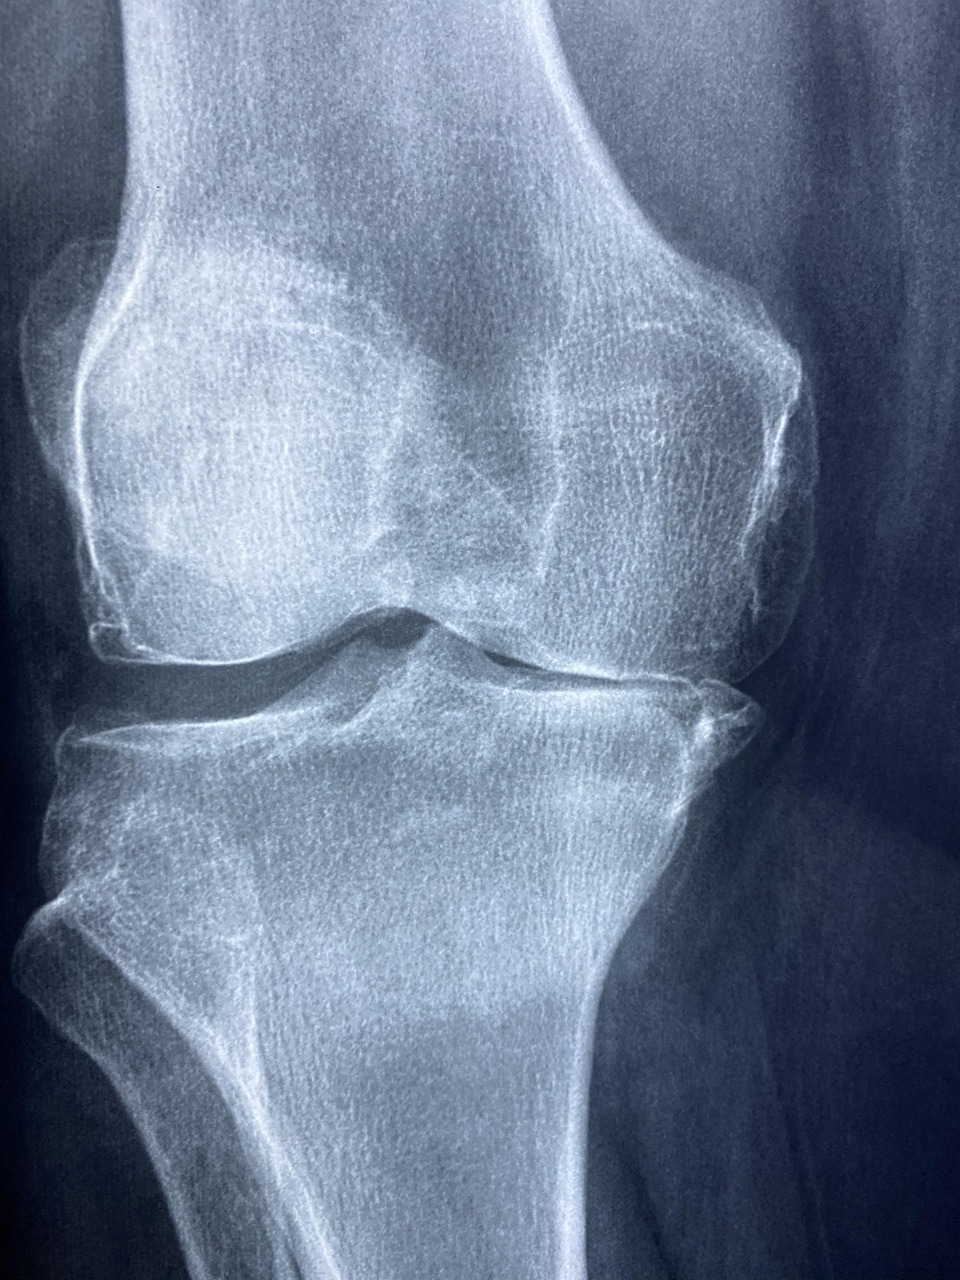

영상 소견: 관절 간격 소실, 골극, 낭종, 연골 전층 손상, 중등도 이상 변형(정강이 내반, 대퇴골 경부 변형 등).

영상: 단순 X-ray(정자세·부하 촬영), 필요 시 CT/MRI로 골변형·연부조직 평가.